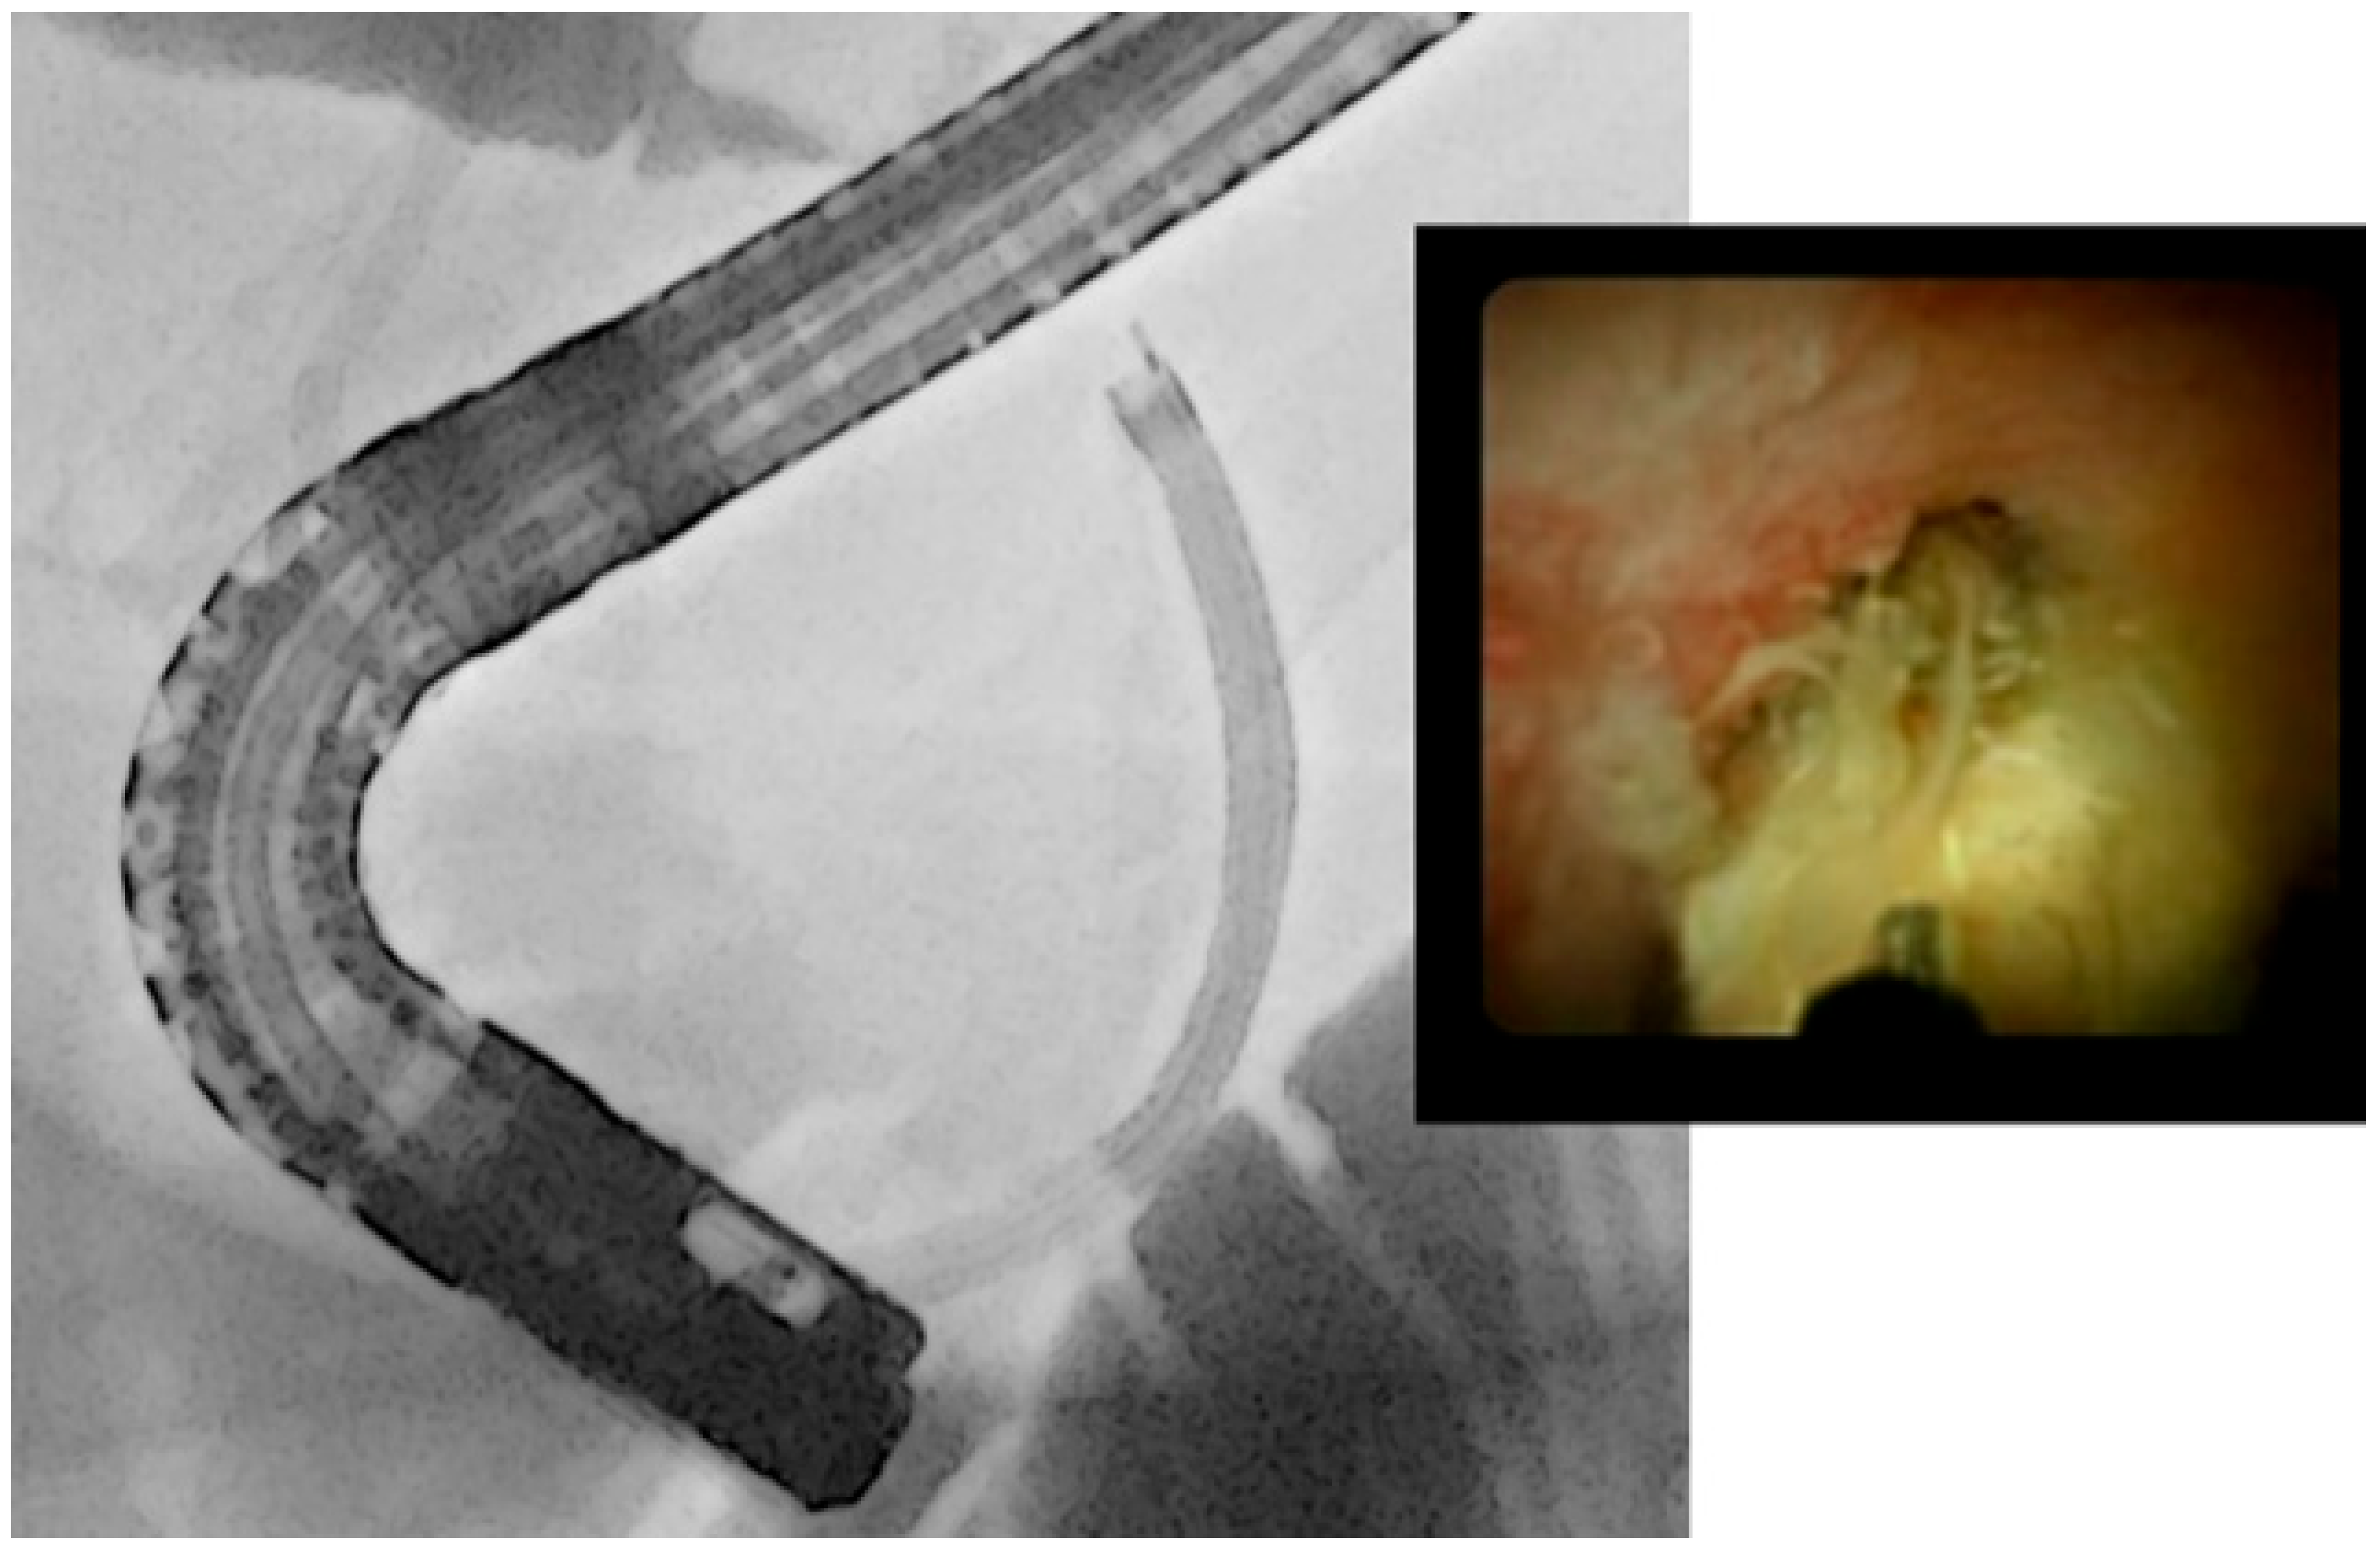

- Kamiyama, R.; Ogura, T.; Okuda, A.; Miyano, A.; Nishioka, N.; Imanishi, M.; Takagi, W.; Higuchi, K. Electrohydraulic Lithotripsy for Difficult Bile Duct Stones under Endoscopic Retrograde Cholangiopancreatography and Peroral Transluminal Cholangioscopy Guidance. Gut Liver 2018, 12, 457–462. [Google Scholar] [CrossRef]

- Oh, C.H.; Dong, S.H. Recent advances in the management of difficult bile-duct stones: A focus on single-operator cholangioscopy-guided lithotripsy. Korean J. Intern. Med. 2021, 36, 235–246. [Google Scholar] [CrossRef]

- Liu, R.; Zhang, B.; Liu, D. Peroral cholangioscopy-guided laser lithotripsy to treat regional hepatolithiasis without stricture. Dig. Endosc. 2018, 30, 537–538. [Google Scholar] [CrossRef]

- Mansilla-Vivar, R.; Alonso-Lázaro, N.; Argüello-Viudez, L.; Ponce-Romero, M.; Bustamante-Balen, M.; Pons-Beltrán, V. New management of hepatolithiasis: Can surgery be avoided? (with video). Gastroenterol. Hepatol. 2020, 43, 188–192. [Google Scholar] [CrossRef]